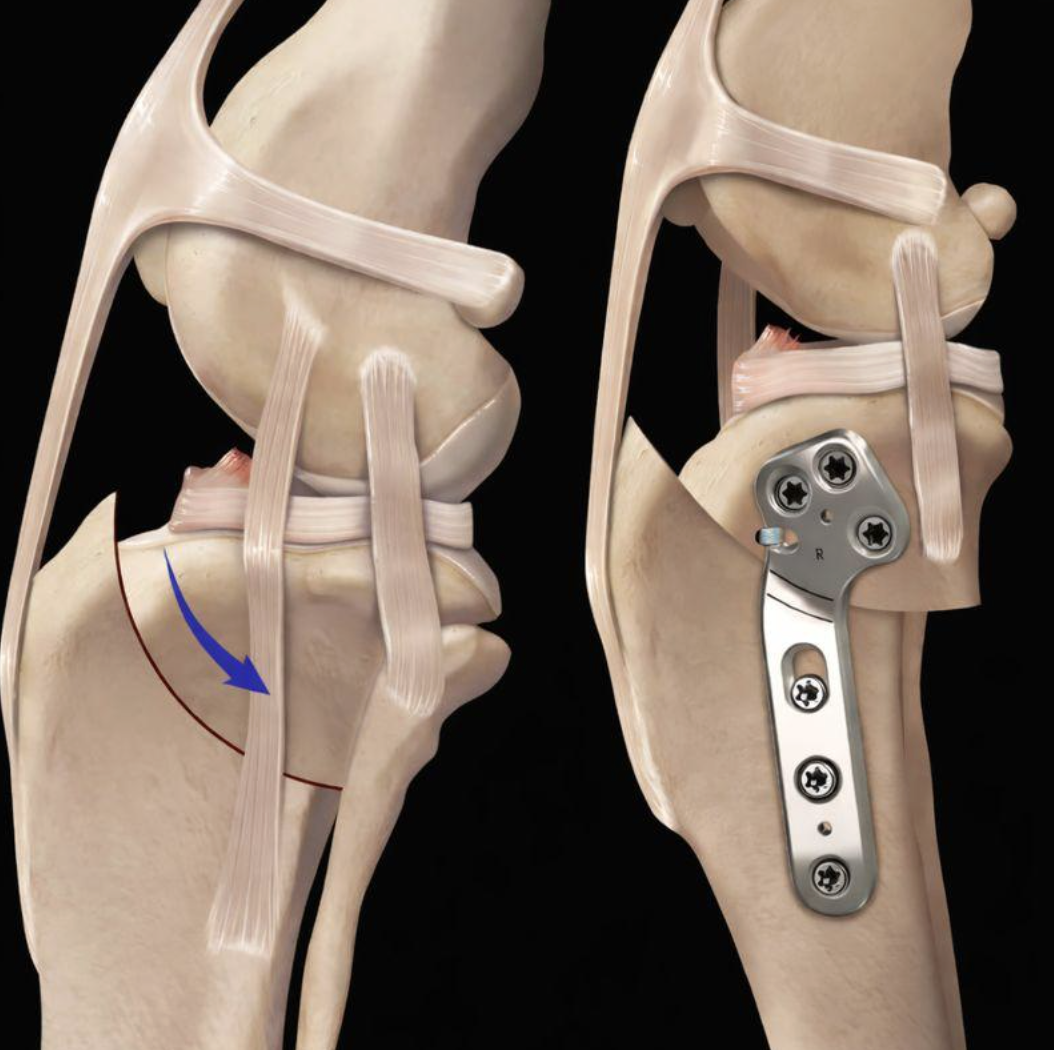

Salter Harris type IV de l’humerus distal sur Yuki un chihuahua de 3 mois (face et profil)

Fracture Salter Harris type IV de l’humerus distal sur Yuki traité par vis intercondylienne et une plaque LCP latérale. (face et profil )